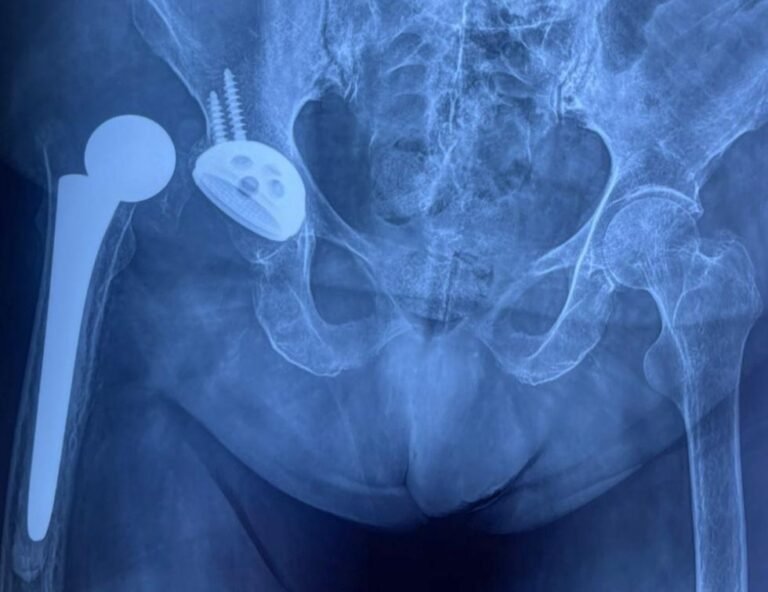

-Pacientes con cirugía de columna con tornillos o fusión lumbar

La copa metálica del sistema de doble movilidad que va incrustada en el hueso es completamente lisa en la superficie cóncava y se articula con la cabeza de polietileno.

El sistema cuenta con dos cabezas, una entra a presión en otro, se mueven entre ellas, y este conjunto se mueve además dentro de la copa metálica adherida al hueso.